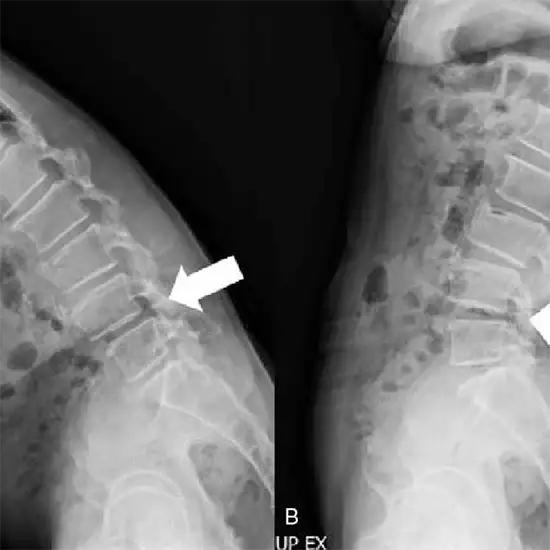

Dorsolumbar Spine Flexion and Extension

An X-ray of the dorsal-lumbar spine is used to view the vertebrae of the lower back (thoracic and lumbar spinal column) and their intervertebral discs and the surrounding soft tissues such as skin and muscles.